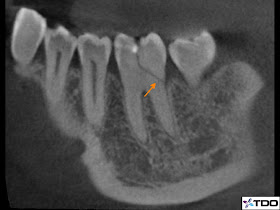

![]() |

| Figure 2: CT scan clearly illustrating the extent of the fracture. |